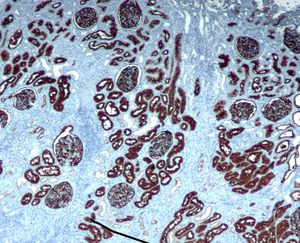

Immunohistochemistry (IHC) is the most common application of immunostaining. It involves the process of selectively identifying antigens (proteins) in cells of a tissue section by exploiting the principle of antibodies binding specifically to antigens in biological tissues.[1] IHC takes its name from the roots "immuno", in reference to antibodies used in the procedure, and "histo", meaning tissue (compare to immunocytochemistry). Albert Coons conceptualized and first implemented the procedure in 1941.[2]

Immunohistochemical staining is widely used in the diagnosis of abnormal cells such as those found in cancerous tumors. Specific molecular markers are characteristic of particular cellular events such as proliferation or cell death (apoptosis).[3] Immunohistochemistry is also widely used in basic research to understand the distribution and localization of biomarkers and differentially expressed proteins in different parts of a biological tissue.

Visualising an antibody-antigen interaction can be accomplished in a number of ways. In the most common instance, an antibody is conjugated to an enzyme, such as peroxidase, that can catalyse a colour-producing reaction (see immunoperoxidase staining).[4] Alternatively, the antibody can also be tagged to a fluorophore, such as fluorescein or rhodamine (see immunofluorescence).

Reporter molecules vary based on the nature of the detection method, the most popular being chromogenic and fluorescence detection mediated by an enzyme or a fluorophore, respectively. With chromogenic reporters, an enzyme label reacts with a substrate to yield an intensely colored product that can be analyzed with an ordinary light microscope. While the list of enzyme substrates is extensive, alkaline phosphatase (AP) and horseradish peroxidase (HRP) are the two enzymes used most extensively as labels for protein detection. An array of chromogenic, fluorogenic and chemiluminescent substrates is available for use with either enzyme, including DAB or BCIP/NBT, which produce a brown or purple staining, respectively, wherever the enzymes are bound. Reaction with DAB can be enhanced using nickel,[7] producing a deep purple/black staining.